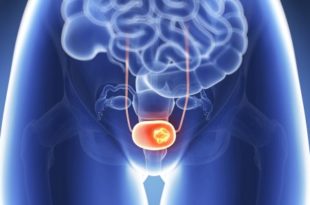

Diagnózis és a húgyhólyag sebészeti technikák, módszerek

Amikor a fájdalom, görcsök, égető vizelés, gyakori vagy visszahúzó késleltetés lesz hozzárendelve, különböző diagnosztikai eljárások. Módszerek a laboratóriumi vizsgálatok a vér-és vizeletvizsgálat, ultrahang mochevika, CT és az MRI, hólyagtükrözés, X-ray meghatározni az oka a romlás állam a urogenitális rendszer. Igénylő betegségek sebészet - daganatok, kövek, polipok, sipolyok, fekélyes cystitis, endometriózis. Mivel a lehetőségét a korai felismerés a szervi technikával gyakran használt, ám a kapcsolat a környezettel minimálisan invazív technikákat alkalmazunk a húgycsövön keresztül. A műveletek típusai - tsistolitolapaksiya (kövek eltávolítása), részleges eltávolítását a tumoriézió vagy a hashártya, hüvely, vagy a húgycső.